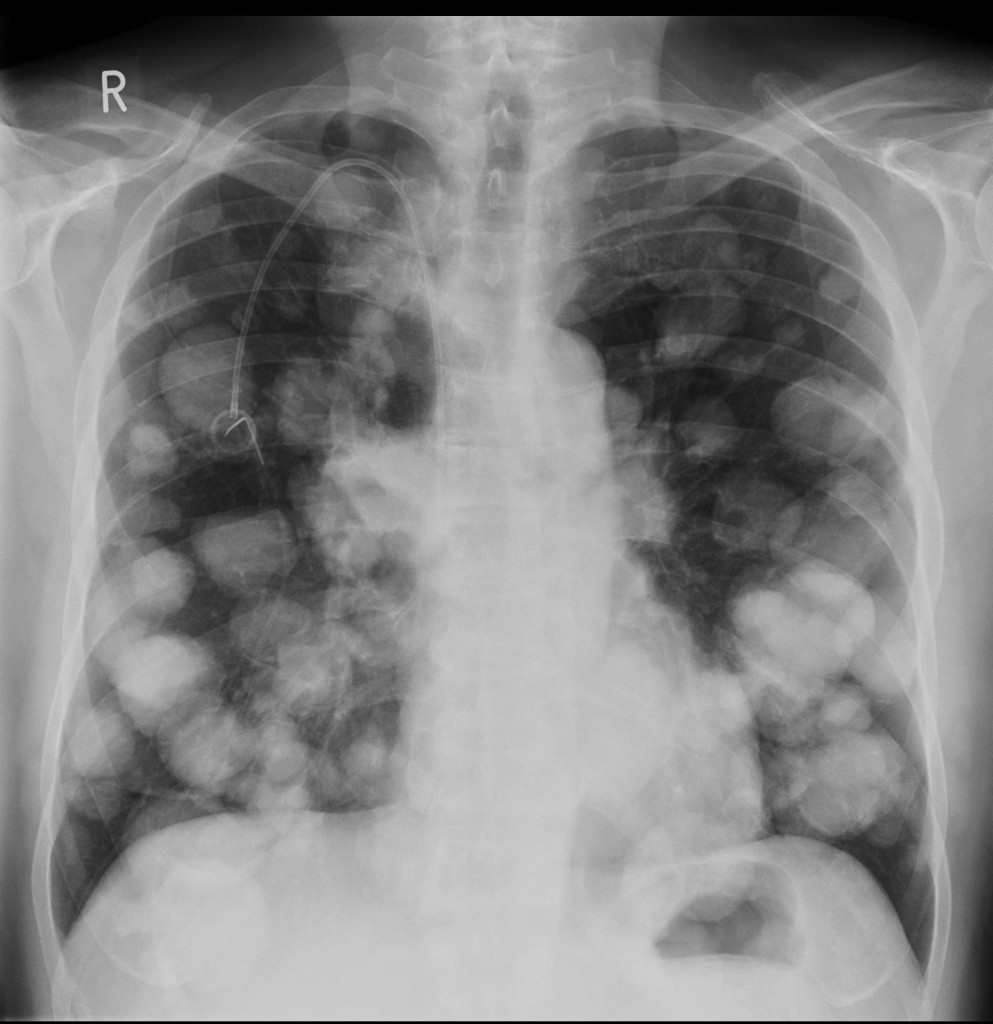

What is the classic feature of renal cell carcinoma on CXR?

Cannonball metastases